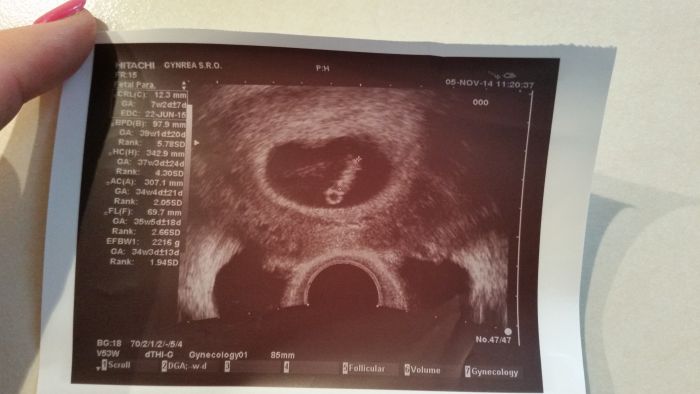

Holky, tak já byla včera poprvé u dr. a měla bych být 7+2tt, srdíčko hezky bilo, ale utz jsem si musela zaplatit, prý na bezplatný mám nárok až za 14 dní..přitom s prvním mimčem, mi udělali utz hned v 6 tt a nic jsem neplatila..zase tahanice o peníze, mi přijde, nebo to máte taky tak nějaká? Prý mám nárok jen na 3 utz za těhu,když teda neberu screen., ale ten mi stejně dělají v Gennetu a ten první stojí 1200,-. Ale než čekat dalších 14 dní, tak jsem řekla, že si ho zaplatím. Jestli bude vše ok, tak by nám za 14 dní dali průkazku.

Fotečka je krásná, je tam vše krásně vidět, já tak pěknou nemám, ani tam není tolik údajů jak na tom tvým UTZ

Zdravim holky, moc sem neprihazuji prispevkama, ale ctu vas pravidelne.jsem spis na fcb.dnes jsem byla na prvni kontrole a jsem 8+3 a termin mi posunul na 15.6.ukazal doktor vse, rucicky, nozicky a srdicko.mimi ma 18, 8 mm.byla jsem moc rada ze je vse v poradku.pristi tyden na odbery a pro prukazku.prikladam fotecku.